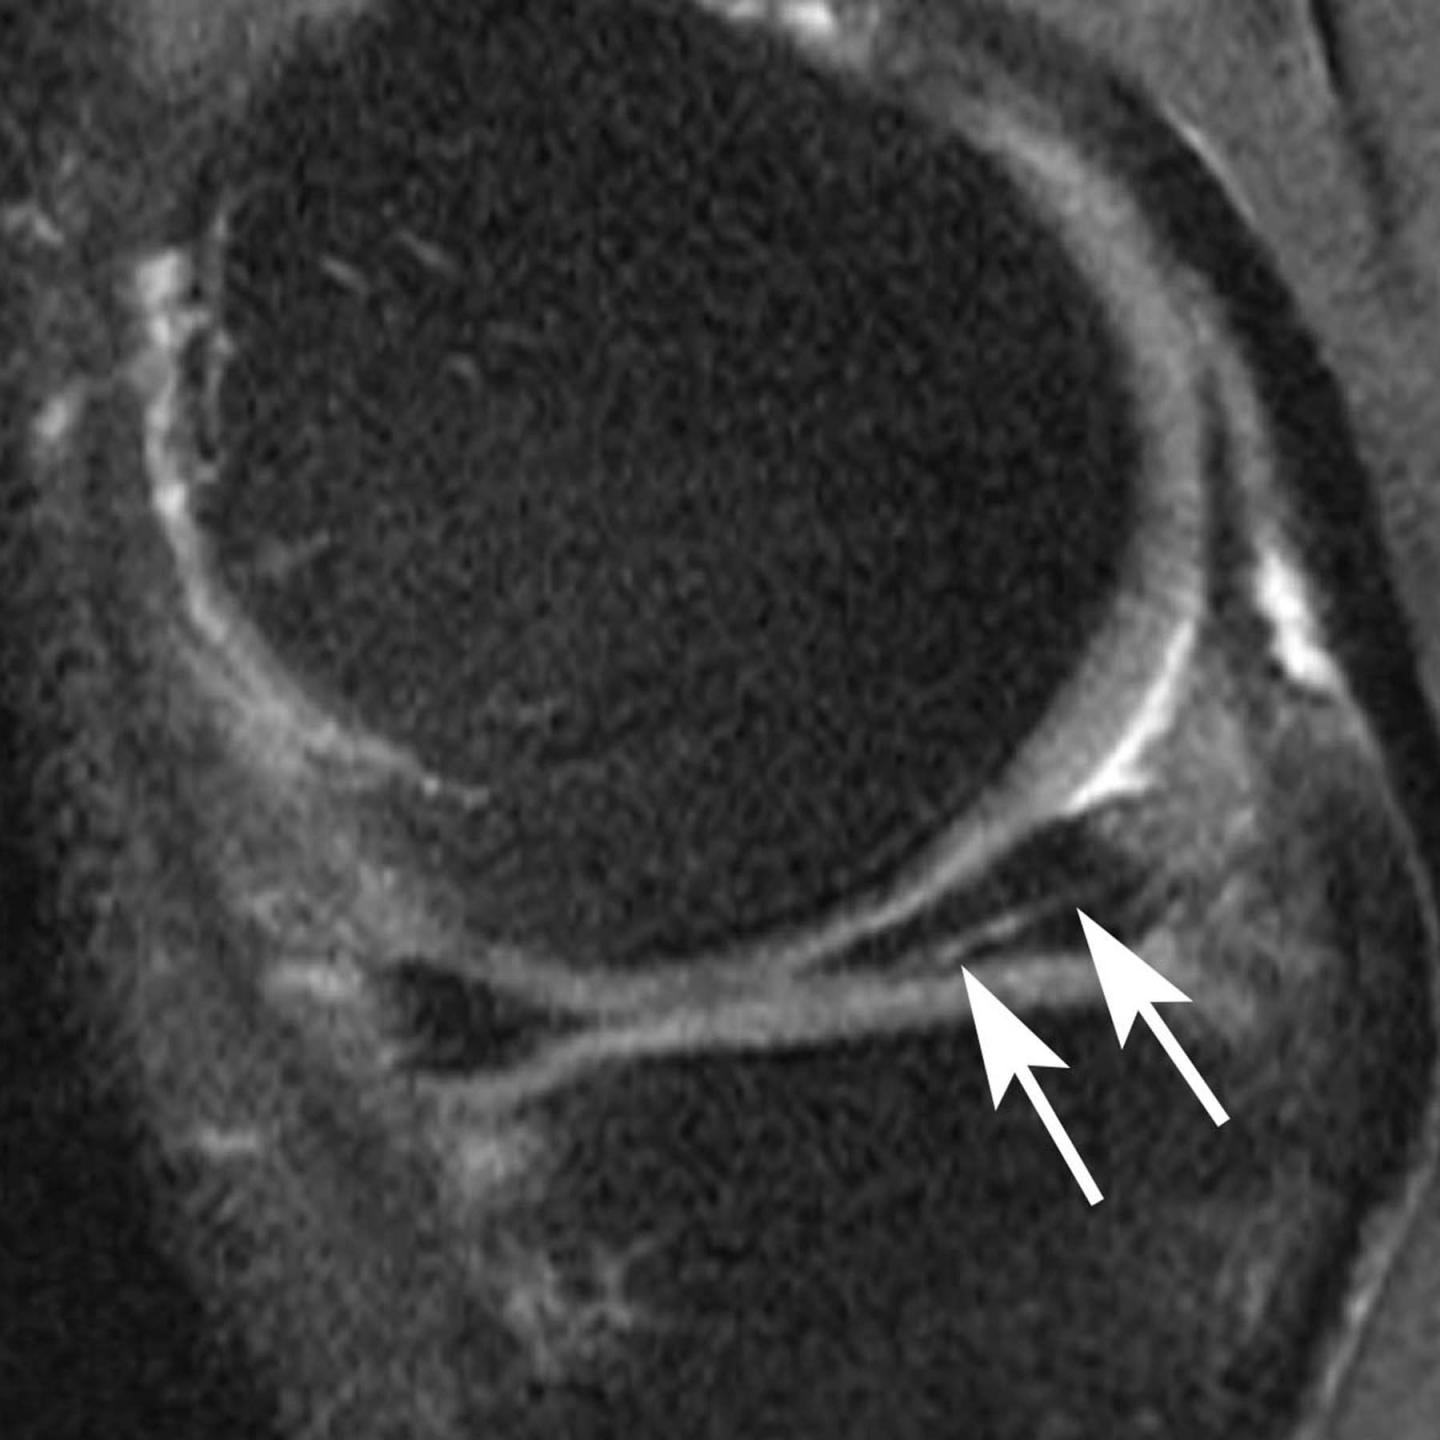

The new study focused on the meniscus, a wedge-shaped piece of cartilage in the knee that acts as a shock absorber between the femur, or thighbone, and tibia, or shinbone. The two menisci in each knee also play an important role in joint stability. Meniscal tears are among the most common knee injuries, and surgery is often performed to alleviate pain.

The researchers studied magnetic resonance imaging (MRI) exams of 355 knees that developed osteoarthritis during a five-year period, and a control group that was matched for age, gender, arthritic severity in both knees and BMI. Of all knees, 31 underwent meniscal surgery during the year prior to the arthritis diagnosis, and 280 knees had signs of meniscal damage on MRI but did not have surgery. Also part of the analysis were control cases with no meniscal damage. The researchers assessed the risk of developing arthritis and cartilage loss during the following year for the different groups.